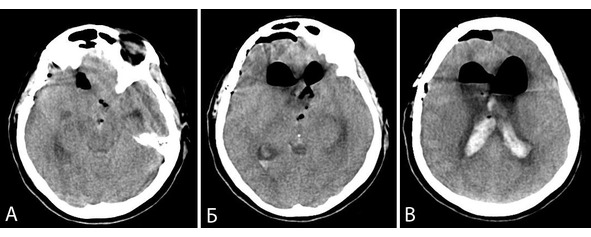

Из анамнеза известно, что в течение трех лет страдал от эпилептических приступов (по типу парциальных и сложных парциальных). Больной обследован по месту жительства, выявлено объемное образование левой височной доли, трактованное как злокачественная опухоль (рисунок 35). Проведено комбинированное адъювантное лечение: облучение (50 Гр) + химиотерапия (6 курсов).

Рисунок 35. Клиническое наблюдение 6. МРТ больного с каверномой медиальных отделов левой височной доли. А – Т2 режим, аксиальная проекция, Б – Т1 режим, сагиттальная проекция, В – Т2 режим фронтальная проекция.